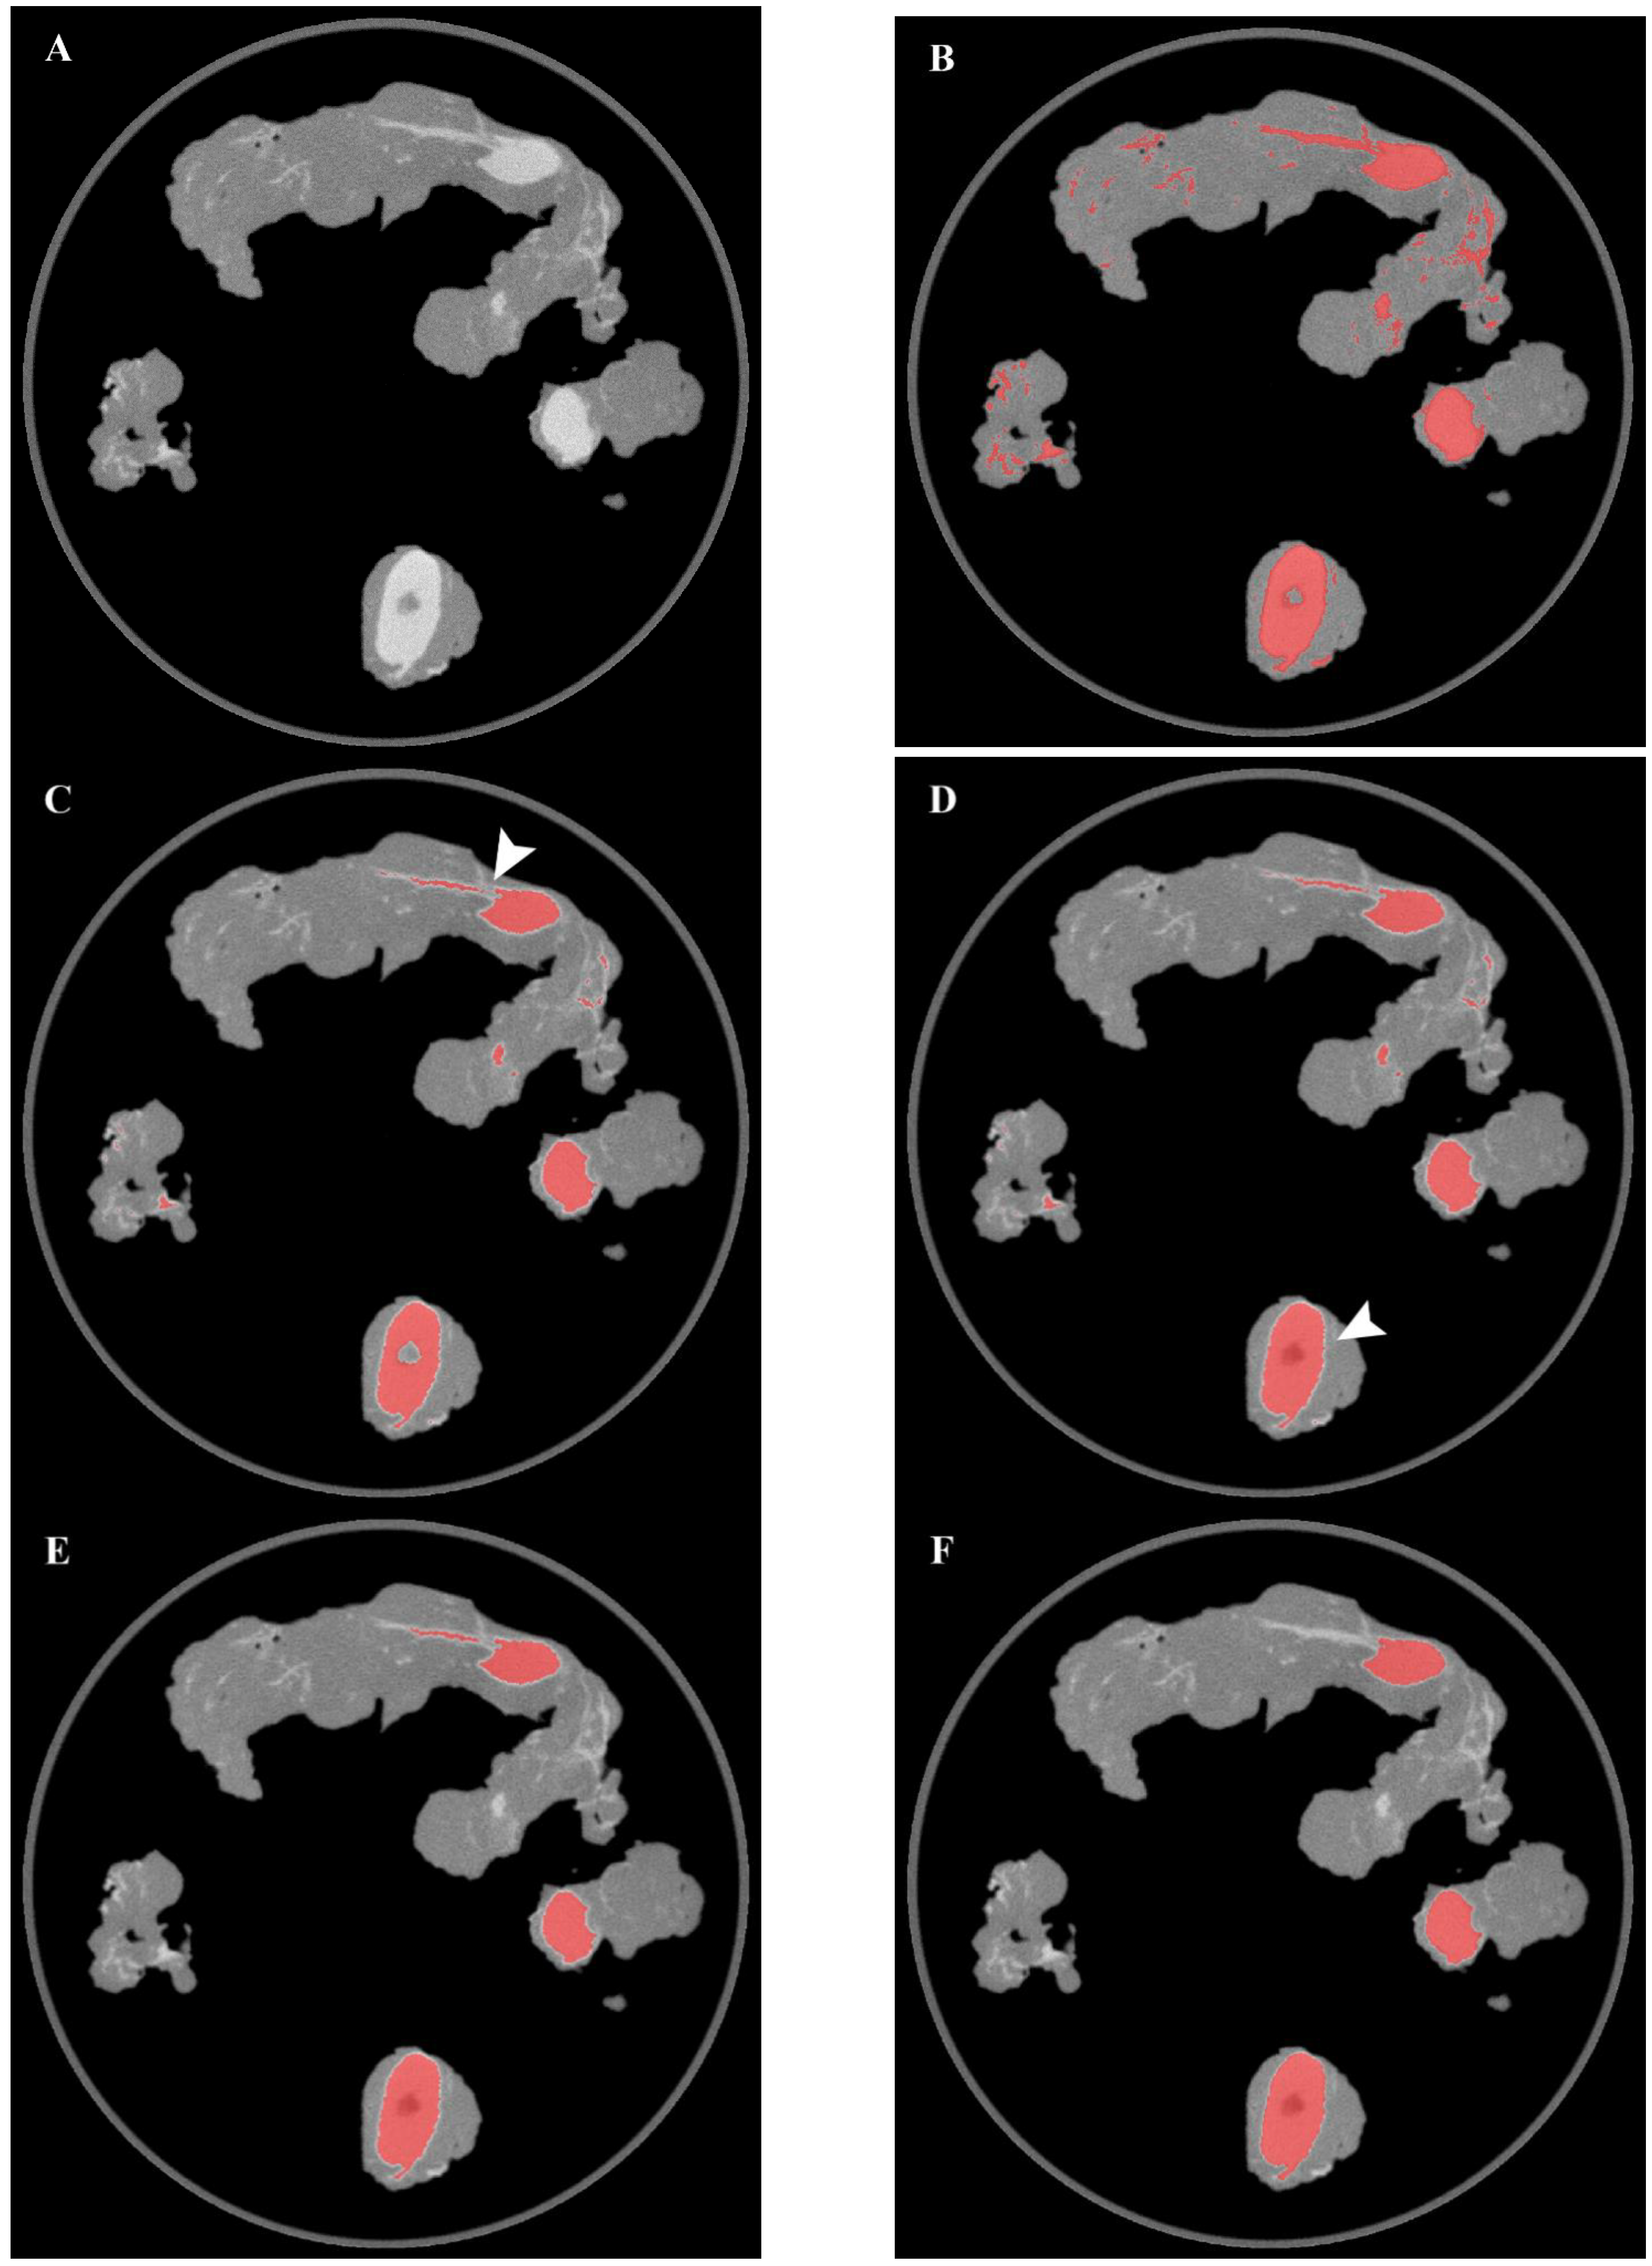

| Specimens | Precision | Recall | Dice Coefficient | Jaccard Index |

| Left proximal external iliac | 0.98 | 0.78 | 0.87 | 0.77 |

| Left obturator (1) | 0.98 | 0.84 | 0.90 | 0.82 |

| Left obturator (2) | 0.95 | 0.82 | 0.88 | 0.79 |

| Average metrics | Precision | Recall | Dice Coefficient | Jaccard Index |

| Micro average | 0.97 | 0.81 | 0.88 | 0.79 |

| Macro average | 0.97 | 0.81 | 0.88 | 0.79 |

| Weighted average | 0.97 | 0.81 | 0.88 | 0.79 |

| Right distal external iliac | 0.99 | 0.72 | 0.83 | 0.71 |

| Right proximal external iliac | 0.99 | 0.64 | 0.78 | 0.64 |

| Right obturator | 1.00 | 0.72 | 0.84 | 0.72 |

| Micro average | 0.99 | 0.68 | 0.81 | 0.67 |

| Macro average | 0.99 | 0.69 | 0.81 | 0.69 |

| Weighted average | 0.99 | 0.68 | 0.80 | 0.67 |